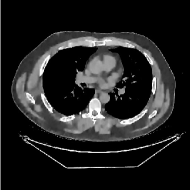

Fig. 7 studies the influence of regularization parameters and on PWLS-ST-. Given a fixed hard-shrinkage parameter , a larger value better removes noise (or unwanted artifacts), but too large can oversmooth reconstructed images; compare Fig. 7(a) and Fig. 7(b). Given a fixed regularization parameter , a larger value leads to lower sparsity in sparse codes and achieves better noise reduction, but too large can remove some edges (e.g., in bone regions); compare Fig. 7(c) and Fig. 7(d). In particular, Fig. S.8 in the supplement shows that once the value is properly chosen, PWLS-ST- is robust to a wide range of values.